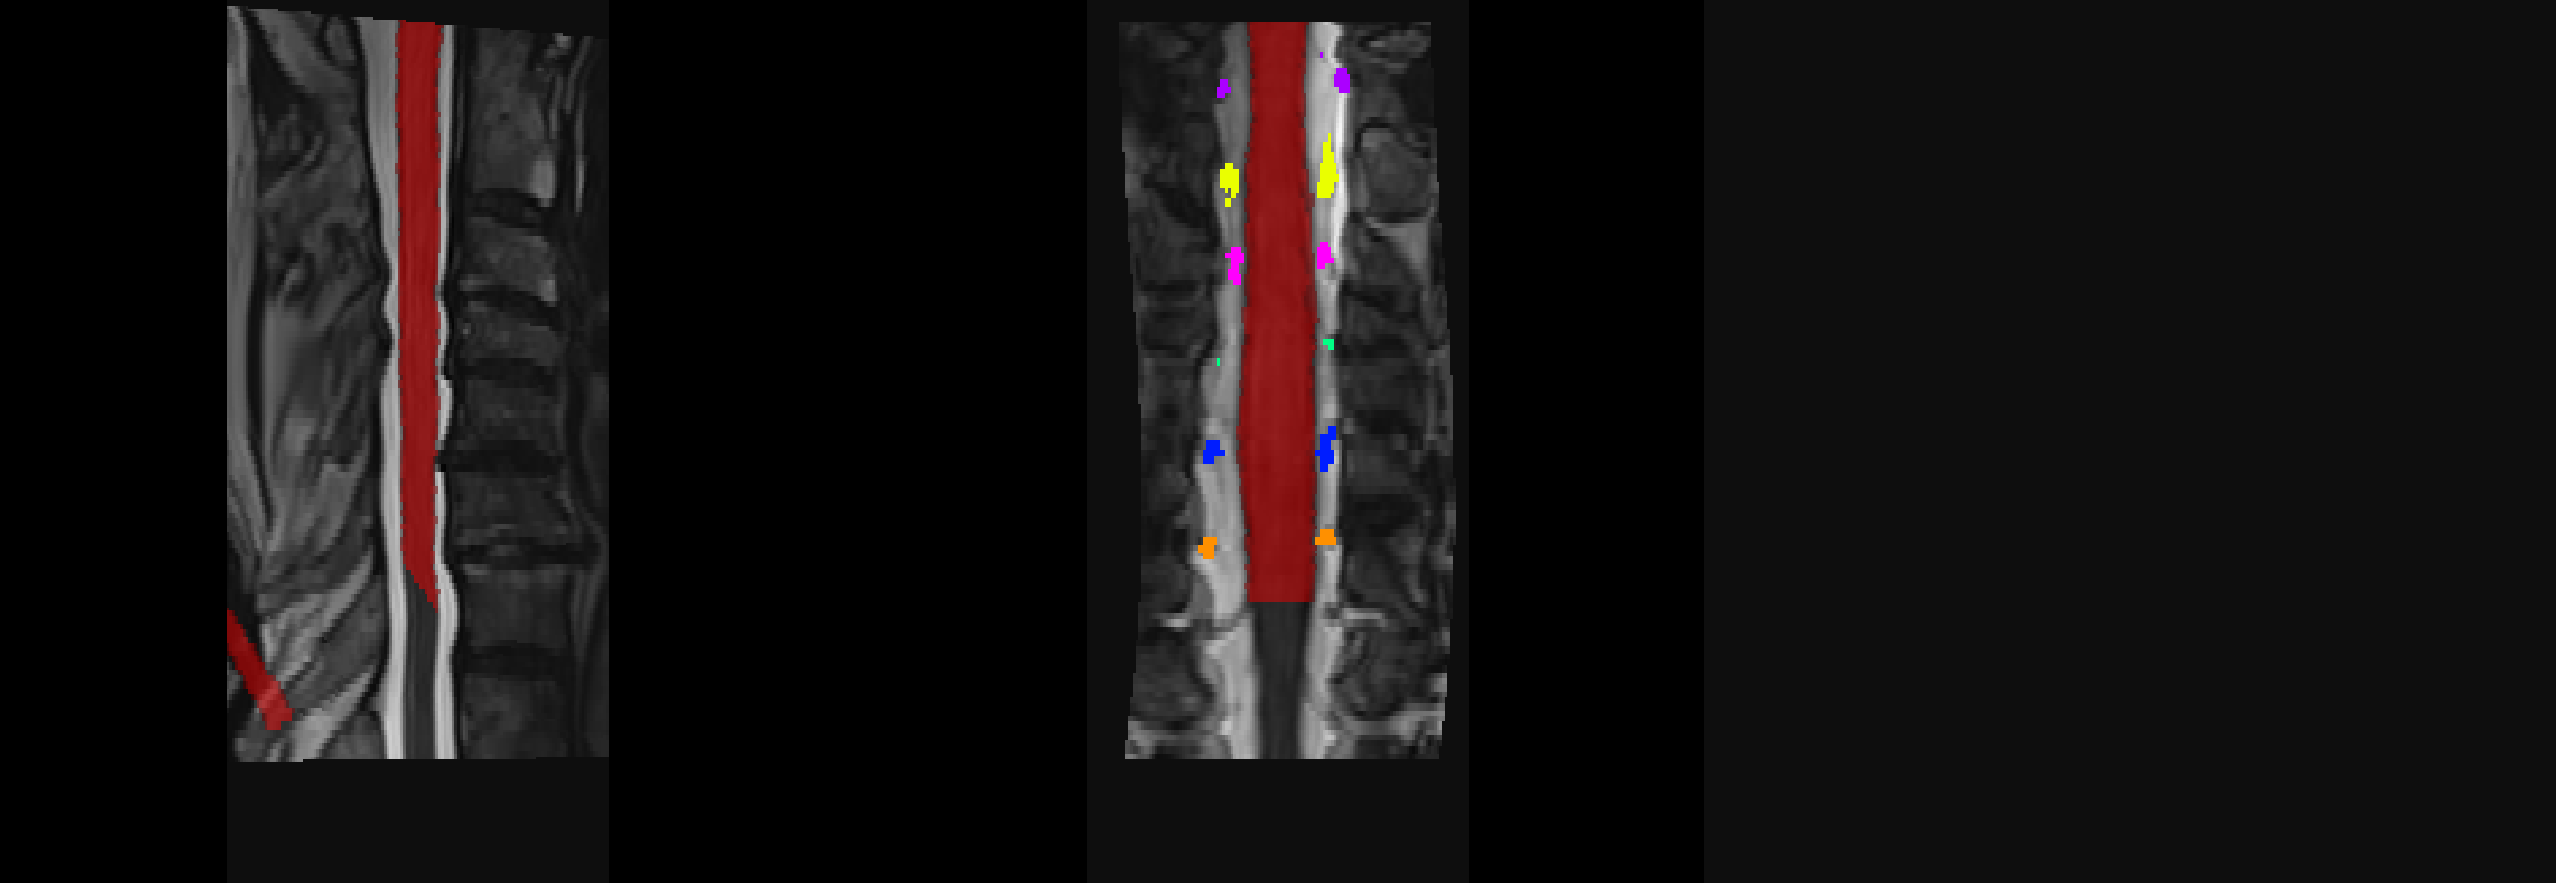

An additional consideration: You’re using -lrootlet, which, for step=0, aligns all rootlets between the native space and the PAM50 space. Since rootlets only go down to C8 spinal level, everything below it is cropped out for subsequent registration steps, hence, the final “native ↔ PAM50” warping field will ignore everything below the C8 spinal level. This is indicated in the sct_register_to_template help:

If more than two labels are used, a non-linear registration will be applied to align the each intervertebral disc between the subject and the template, as described in sct_straighten_spinalcord. This the most accurate method, however it has some serious caveats:

- This feature is not compatible with the parameter

-ref subject, where only a rigid registration is performed.- Due to the non-linear registration in the S-I direction, the warping field will be cropped above the top label and below the bottom label. Applying this warping field will result in a strange-looking registered image that has the same value above the top label and below the bottom label. But if you are not interested in these regions, you do not need to worry about it.

If you’re interested in levels below, consider using disc segmentation instead.